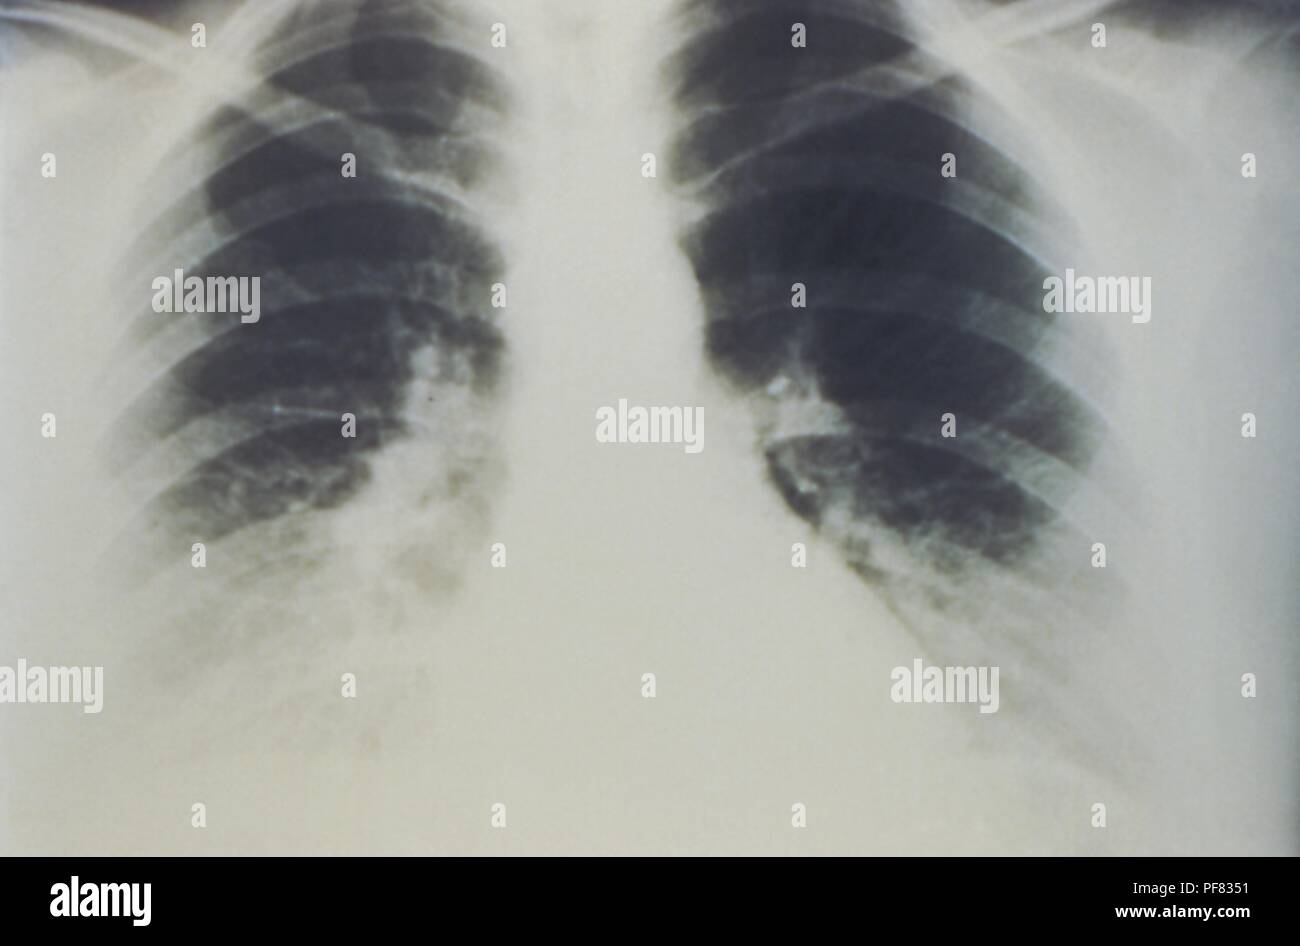

RMPF833F–Mise en scène mi-épanchement pulmonaire bilatéral en raison de syndrome pulmonaire à hantavirus (SPH), révélée dans l'AP La radiographie du thorax, 1994. Image courtoisie Centres for Disease Control (CDC) / D. Loren Ketai, M.D. ()

RMPF8351–Premières étapes de l'épanchement pulmonaire bilatéral en raison de syndrome pulmonaire à hantavirus (SPH), révélée dans l'AP La radiographie du thorax, 1994. Image courtoisie Centres for Disease Control (CDC) / D. Loren Ketai, M.D. ()

RMD0NWAJ–Cette radiographie pulmonaire révèle la mi-monté en raison d'épanchement pulmonaire bilatéral syndrome pulmonaire à hantavirus ou radiologique de la SPLI.

RMPF834T–Mise en scène mi-épanchement pulmonaire bilatéral en raison de syndrome pulmonaire à hantavirus (SPH), révélée dans l'AP La radiographie du thorax, 1994. Image courtoisie Centres for Disease Control (CDC) / D. Loren Ketai, M.D. ()